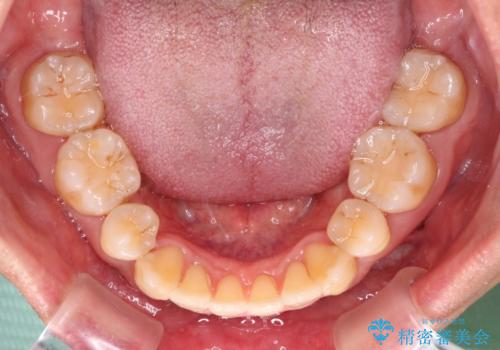

掃除しにくい前歯と閉じにくい口元 目立たないワイヤー装置での抜歯矯正

- 口元の閉じにくさと、前歯のでこぼこの歯並びを気にして来院された患者様です。

口元を積極的に引っ込めるために、上下左右の小臼歯計4本を抜歯することとしました。